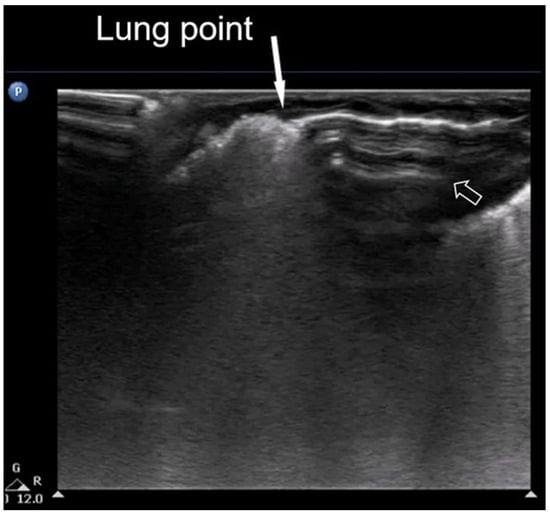

3.1.9. White Lung

LUS is a very useful tool for the follow-up monitoring of neonates. Specifically, as interstitial and alveolar fluids are reabsorbed, B-lines gradually disappear; however, B-lines may persist for much longer in neonates with lower gestational age and in those delivered by cesarean section. When B-lines become confluent, producing a “white lung” pattern, they are typically observed due to the presence of a relatively higher fluid content and a lower glomerular filtration rate [8].

The term “white lung” with respect to neonatal lung ultrasound refers to a sonographic pattern in which the lung fields are entirely filled with compact B-lines in every examined intercostal space, resulting in a uniformly hyperechoic appearance across the lung surface. The compact B-lines are so densely packed that they obliterate A-lines and give the lung a bright, homogenous appearance on ultrasound—hence the term “white lung” (Figure 10).

Figure 10.

White lung: (a) axial plane, (b) longitudinal plane (L: liver), and (c) CXR.

This white appearance during LUS imaging can be caused by a range of problems, including fluid buildup in the air spaces and interstitial space of the lungs, inflammation of the lung tissue, and scarring of the lung tissue. This artifact and pattern are typically associated with widespread pulmonary edema or alveolar–interstitial syndrome and may be seen in conditions such as respiratory distress syndrome (RDS) or Transient Tachypnoea of the Newborn (TTN) [19,30,31,32].

Importantly, white lung differs from other lung ultrasound findings such as localized consolidations or spared areas. It reflects diffuse interstitial–alveolar syndrome and is generally not present in milder pathologies or localized respiratory disease. Recognition of the white lung pattern in LUS is crucial for early diagnosis and severity assessment, particularly in neonates presenting with generalized respiratory distress [30].